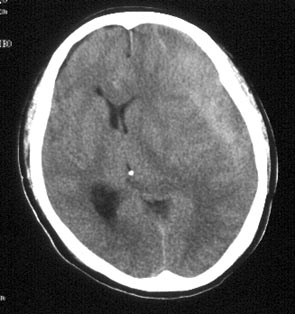

病史:男性,56岁,自觉右侧肢体肌力下降,伴麻木不适半月,逐渐加重。一个月前曾有头部轻微碰伤史,但具体经过不能回忆。

ct平扫:左额及颞顶叶见新月形略高密度血肿影,左右及前后径为2.5x12.7cm。左侧脑室受压变形右移,中线右偏约1.2cm,且密度增高,鞍上池闭塞,中脑受压变形。

ct诊断:左额、颞、顶部慢性硬膜下。